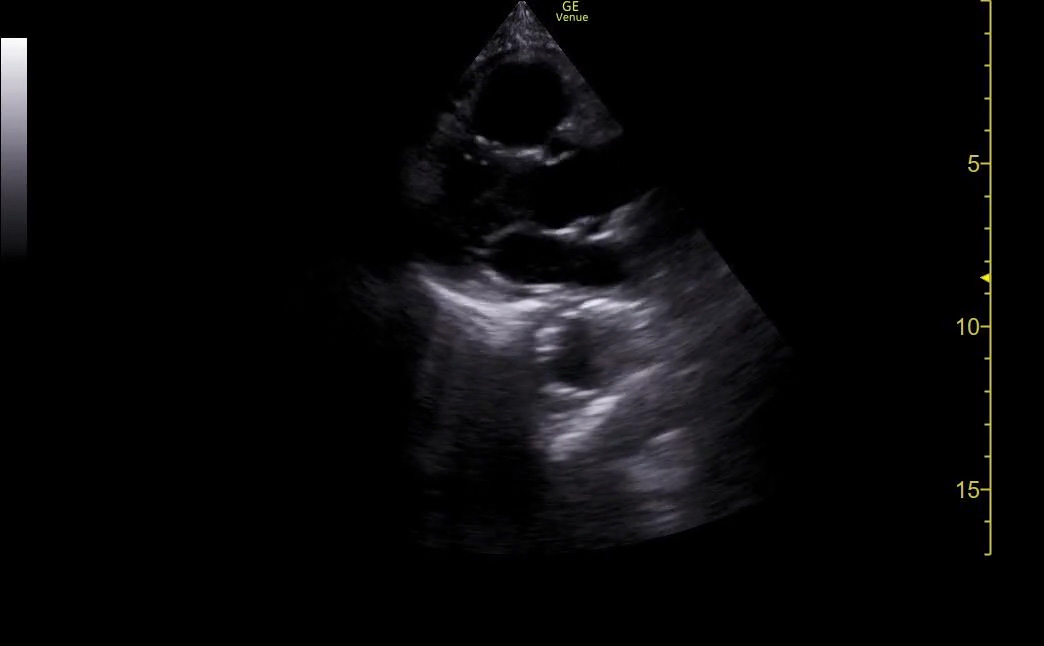

The cardiac preset is another one learners stumble though at times. The apical 4 chamber view almost always requires a different depth setting than the parasteranal views and subxiphoid view.